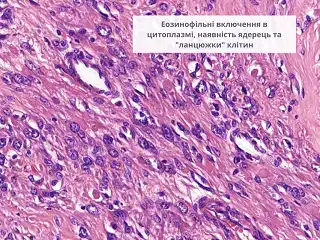

еозинофільні ядерця в клітинах пухлини

яскраво-еозинофільні включення в цитоплазмі

формування “ланцюжків” з пухлинних клітин